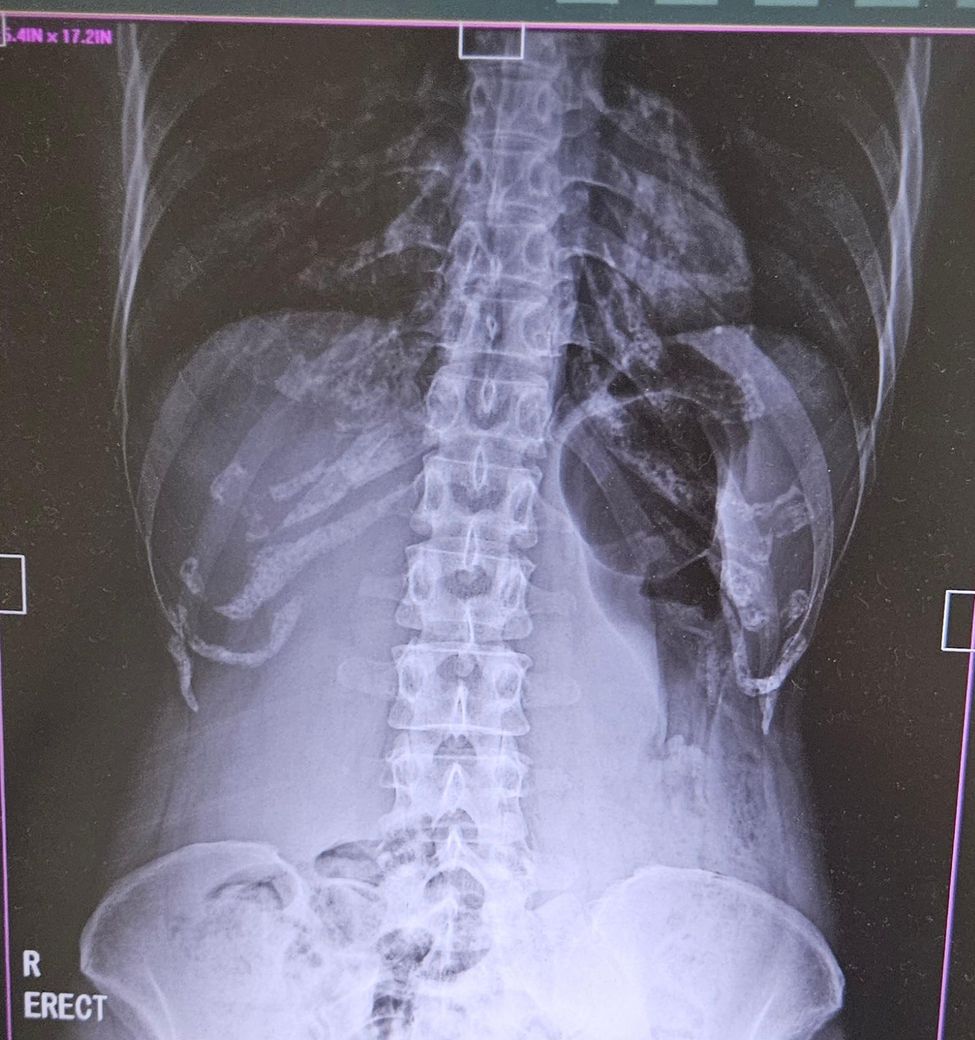

엑스레이 가스찬것 좀 봐주세요 설명부탁드려요

저 가운데 검은 동그랗게 생긴곳이 계속 가스차있는데 이건 왜 그러지요?

위에 가스가 많이 차보이긴 하네요. 관련 대증치료 받아보시길 바랍니다. 내과 내원하여 진료 보시면 될것으로 사료됩니다.

증상 지속시 위내시경 고려해볼 수 있긴 합니다. 답변 도움되었기 바랍니다. 감사합니다.